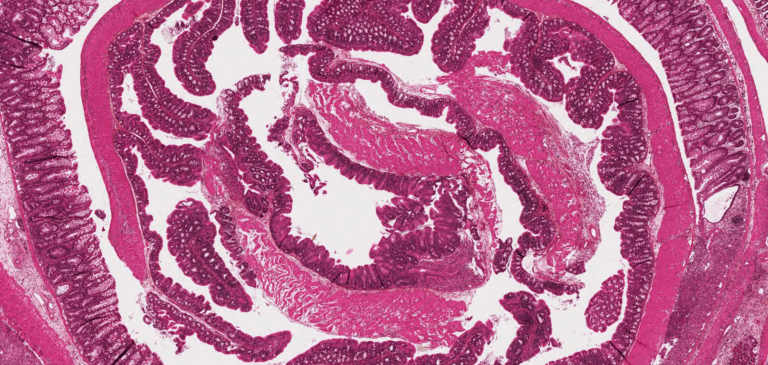

Des services dans les domaines de la protéomique, la constitution des protéines recombinantes, le scannage de tissus et la PCR sont proposées aussi par le CRI